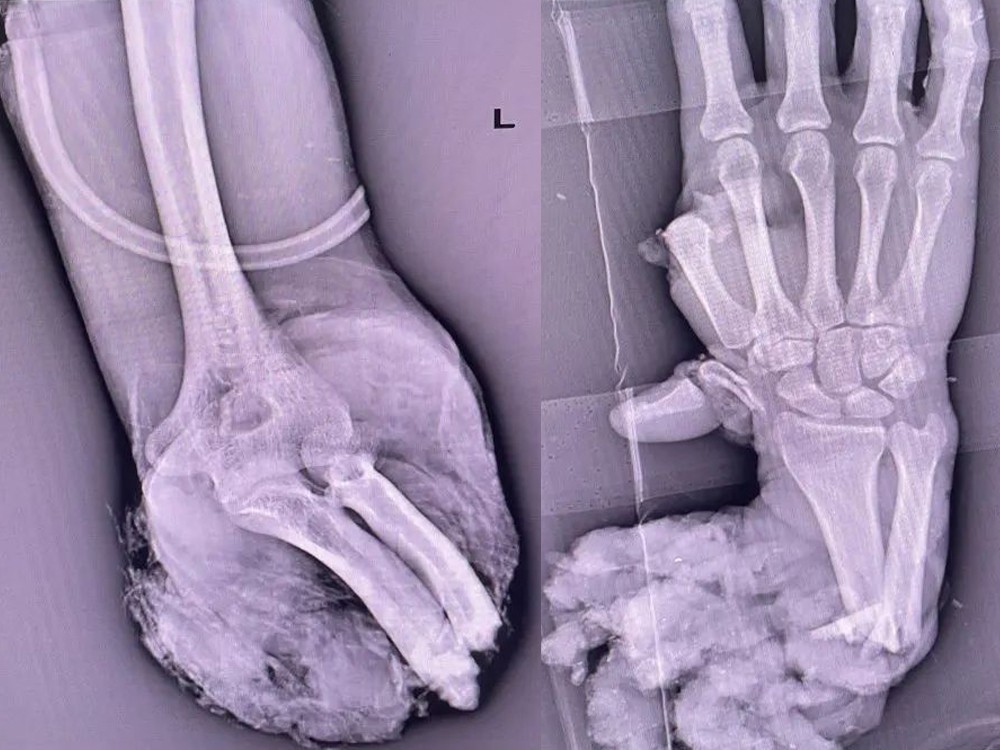

6月3日下午,熊先生在工廠工作時,左上肢不慎被機器絞傷致左前臂毀損性完全離斷。工友看到這樣的場面,立即撥打120送至我院,我院接診后即刻開通綠色通道,急診醫生完善所有術前檢查,立即行急診手術治療!

時間一分一秒的流失,距離事發至送入院已經過去了一個多鐘頭。熊先生左上肢自肘下5cm處完全離斷,近端骨質外露、遠端離斷肢體斷面毀損嚴重、出現大出血休克癥狀。李主任緊急通知骨科團隊、手術室、麻醉科、ICU召開會議,討論保肢的手術治療方案。會議結束后,便立即進行“保肢”手術!各科室迅速準備就緒,隨時準備與時間和死神賽跑。